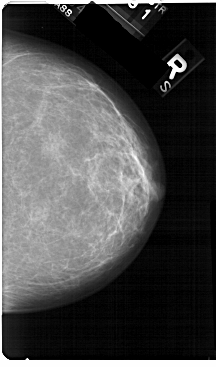

A_1323_1.LEFT_MLO

LEFT_MLO LINES 5491 PIXELS_PER_LINE 3256 BITS_PER_PIXEL 12 RESOLUTION 43.5 OVERLAY